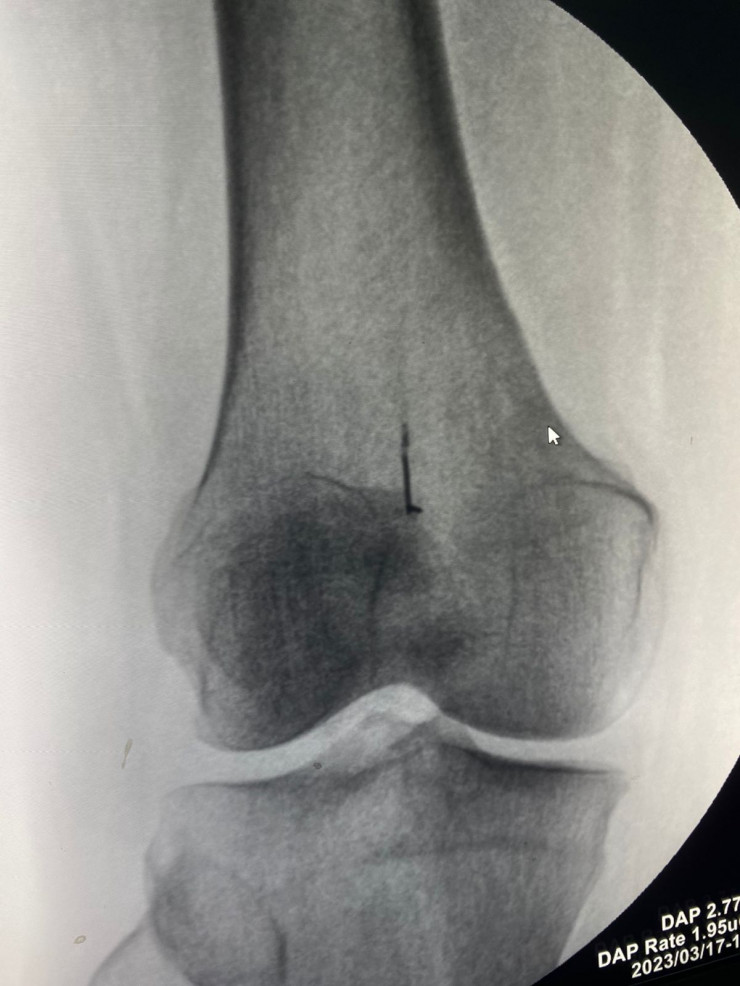

Алматинка 45 лет ходила с иголкой в коленном суставе, передает корреспондент Tengrinews.kz. В Центральную городскую клиническую больницу поступила женщина, у которой в правом коленном суставе почти полвека находилась иголка от швейной машины.

Фото предоставлено пресс-службой ЦГКБ Алматы

Травматологи ЦГКБ провели операцию по удалению инородного тела, которая продлилась полчаса. После операции женщина начала ходить, не хромая, боль исчезла.

Как рассказывает оперирующий травматолог Даулет Чукманов, иголка за много лет уже инкапсулировалась.

"Операция прошла успешно, инородное тело удалено", - отмечает он. В свою очередь женщина поблагодарила врачей за их профессионализм.